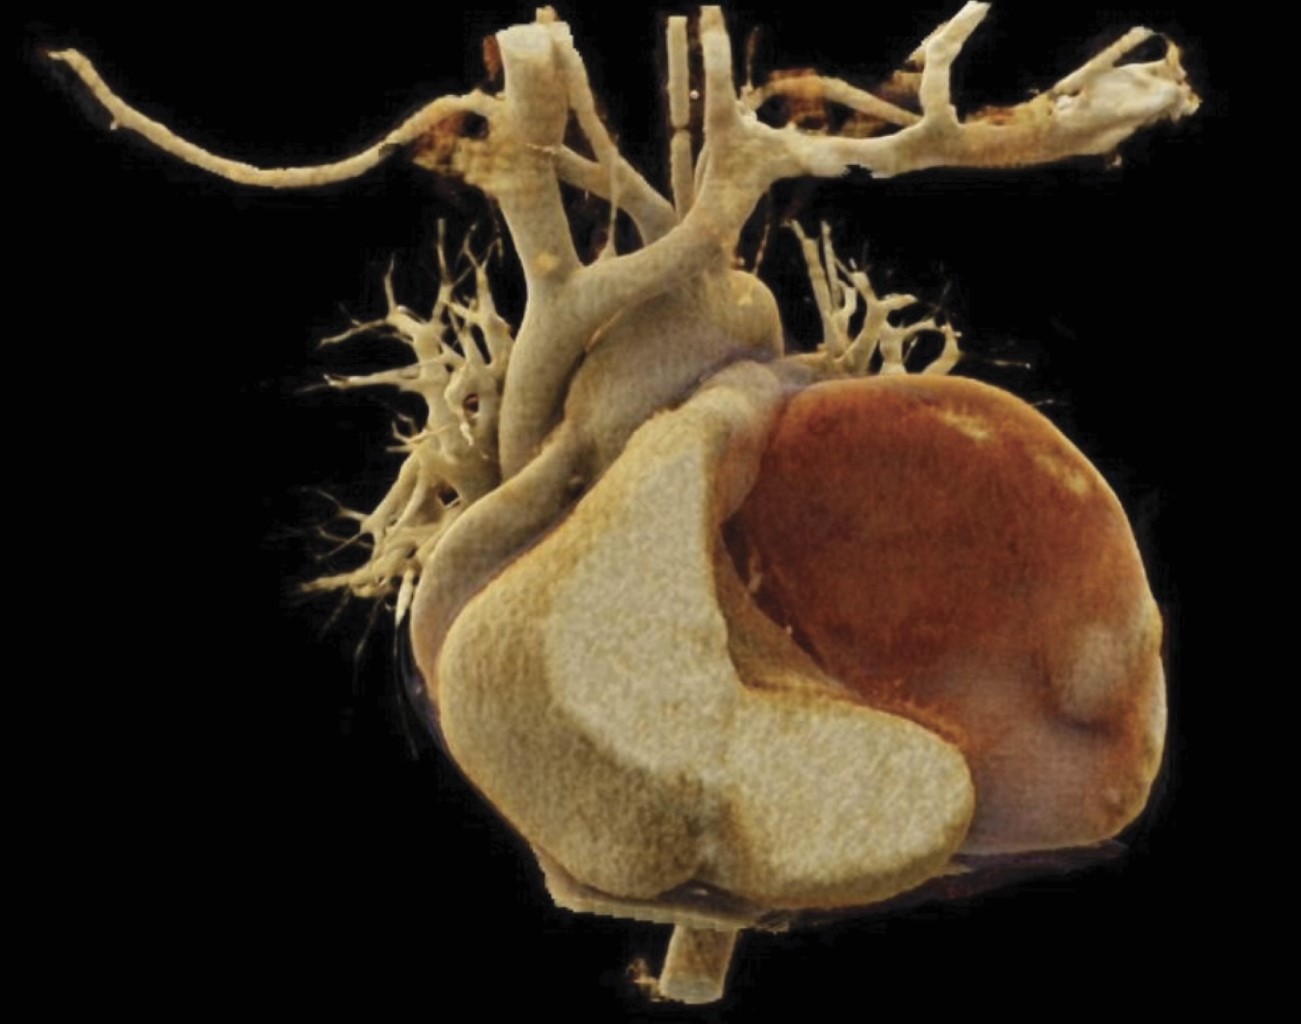

Aneurisma de la orejuela izquierda como causa de evento vascular isquémico: reporte de caso y revisión de la literatura

El aneurisma de la orejuela izquierda es una entidad rara, con pocos casos reportados en la literatura, pero con potenciales implicaciones clínicas significativas. Presentamos el caso de una paciente que debutó con evento vascular isquémico. La evaluación con estudios de imagen evidenció un aneurisma de la orejuela izquierda. Dado el alto riesgo embólico, se decidió el manejo quirúrgico mediante exclusión de la orejuela izquierda. La evolución postoperatoria fue favorable.

Figura 2